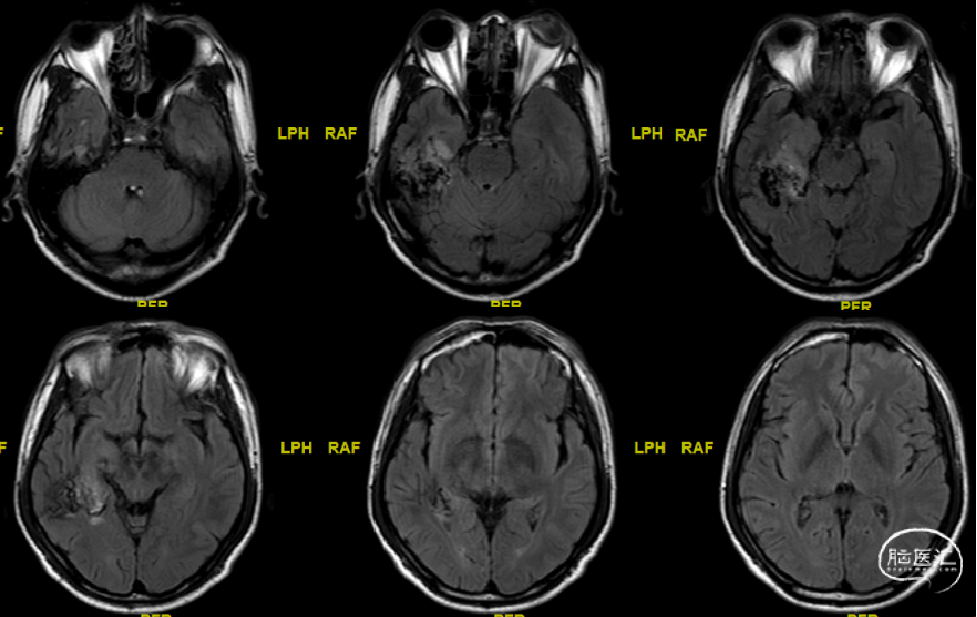

术前MRI